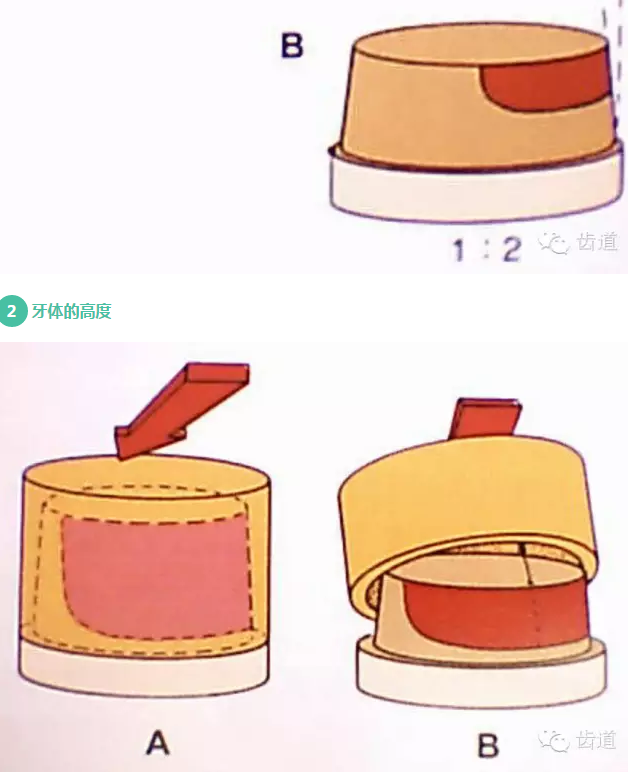

l基牙具有良好的固位形

l基牙具有良好的抗力形

牙的外形及洞形的幾何形狀:主要是牙體制備出一定聚合角度產(chǎn)生的阻擋作用